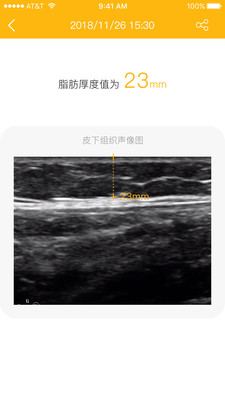

超声波原理的可以快速测量人体皮下脂肪厚度的智能设备

【操作简单,2s出结果】置于测量处,,按下按键,2s输出脂肪厚度数值

可以记录用户的测量数据,包括测量时间、测量部位、脂肪厚度等,方便用户进行数据管理和分析。